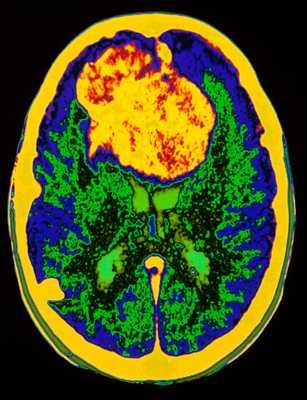

![опухоль мозга в цвете]()

МРТ головного мозга. Аксиальная Т2-взвешенная МРТ. Цветовая обработка изображения. Опухоль мозга.

При дифференциальной диагностике опухолей головного мозга надо учитывать многие факторы включая эпидемиологические и диагностические. Золотым стандартом их выявления служит МРТ головного мозга. Многие центры МРТ СПб берутся за эту задачу, но мы рекомендуем Вам обследоваться именно у нас. При МРТ в СПб в дифференциальной диагностике опухолей в высоком поле и на открытом МРТ мы учитываем многие признаки, включая следующие: